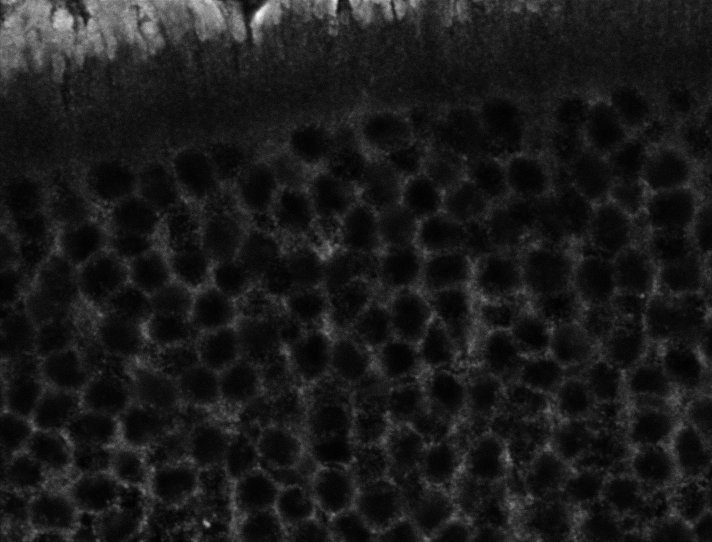

Healthy Eye

Healthy Choroid

Unhealthy Choroid